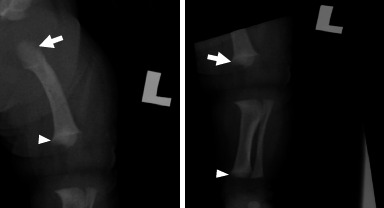

软骨发育不全是一种导致肢体缩短的遗传性疾病,是不成比例侏儒症最常见的形式。产前可通过超声检查诊断,产后可通过临床和放射学检查诊断。目前,越来越多的受影响的胎儿在产前诊断,因为产前超声检查是常规进行在初级保健设置。在此,我们提出一个健康的26岁初产妇,在妊娠晚期,根据她的产前超声检查结果,被诊断为软骨发育不全。出生后,婴儿的临床和放射检查结果证实了这一诊断,显示长骨缩短。本病例强调了在初级保健机构的常规妊娠晚期超声检查中识别软骨发育不全软标记的重要性。软骨发育不全的早期诊断是重要的,以确保及时转诊到三级中心和充分的准备父母为他们的孩子的分娩。

Achondroplasia, a genetic disorder causing limb shortening, is the most common form of disproportionate dwarfism. It can be diagnosed prenatally through sonographic findings and postnatally through clinical and radiological findings. Currently, an increasing number of affected foetuses are diagnosed antenatally since prenatal ultrasonography is routinely conducted in primary care settings. Herein, we present the case of a healthy 26-year-old primigravida who received a diagnosis of achondroplasia for her foetus during the late third trimester based on her prenatal ultrasonographic findings. Following birth, the diagnosis was confirmed by the baby's clinical and radiological findings, which showed shortening of the long bones. This case highlights the importance of recognising the soft markers of achondroplasia during routine third-trimester ultrasonography in primary care settings. Early diagnosis of achondroplasia is important to ensure timely referral to tertiary centres and adequate preparation of parents for the delivery of their baby.